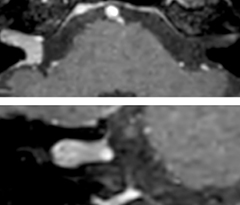

Acute right motor deficit and aphasia

In this patient with acute right motor deficit and aphasia, the b2000 diffusion weighted image is normal. The SWIp image demonstrates more prominent veins in the right hemisphere, which could reflect increased deoxyhemoglobin contents. Fast ASL shows low CBF regions in the left frontal lobe. A follow-up ASL after one hour demonstrates high CBF values in the same area. The final diagnosis was migraine with aura.

Acute right motor deficit and aphasia A

Acute right motor deficit and aphasia B